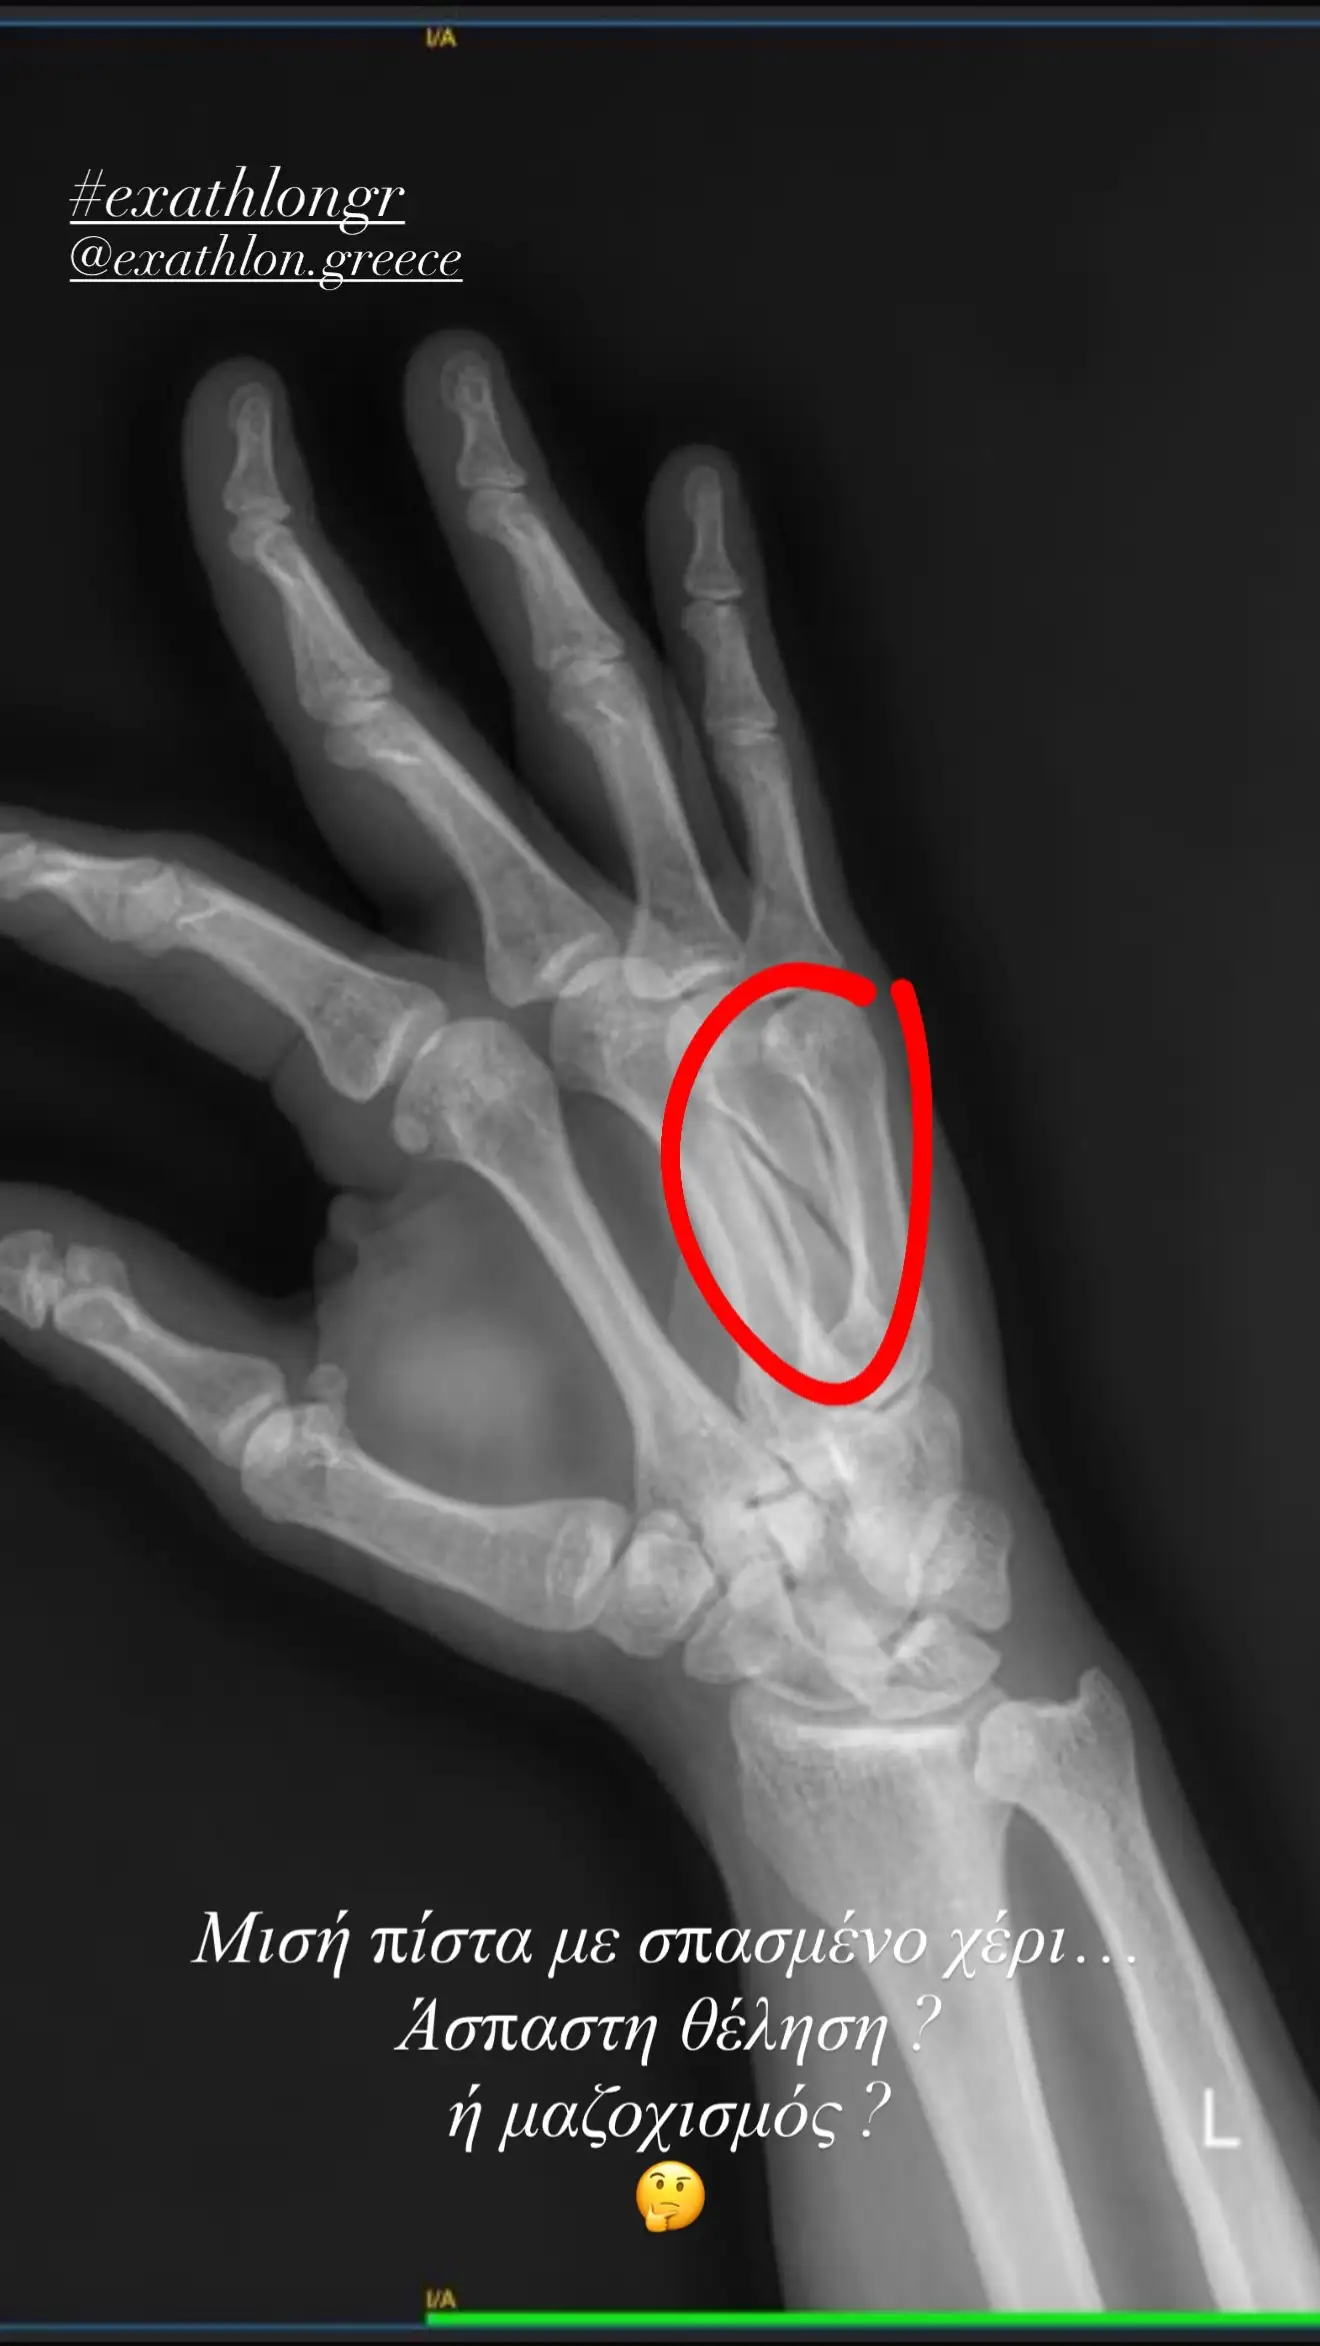

Παράλληλα, δε, ο Στάθης Σχίζας επέλεξε να μοιραστεί με τους διαδικτυακούς του φίλους και μια εικόνα από την ακτινογραφία που αποτυπώνει το σπάσιμο του χεριού του. «Μισή πίστα με σπασμένο χέρι… Άσπαστη θέληση ή μαζοχισμός;» αναρωτιέται χαρακτηριστικά ο πρώην παίκτης του Exathlon στον προσωπικό του λογαριασμό στο Instagram.